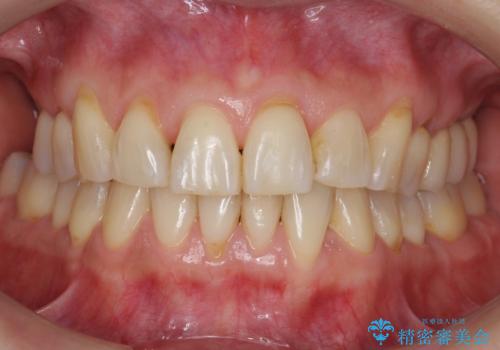

歯並びや奥歯の痛み 色々と治したい 総合歯科診療

担当医 藤巻太一朗

インプラント治療・セラミック治療を含む 全顎的虫歯治療

担当医 大元洋佑